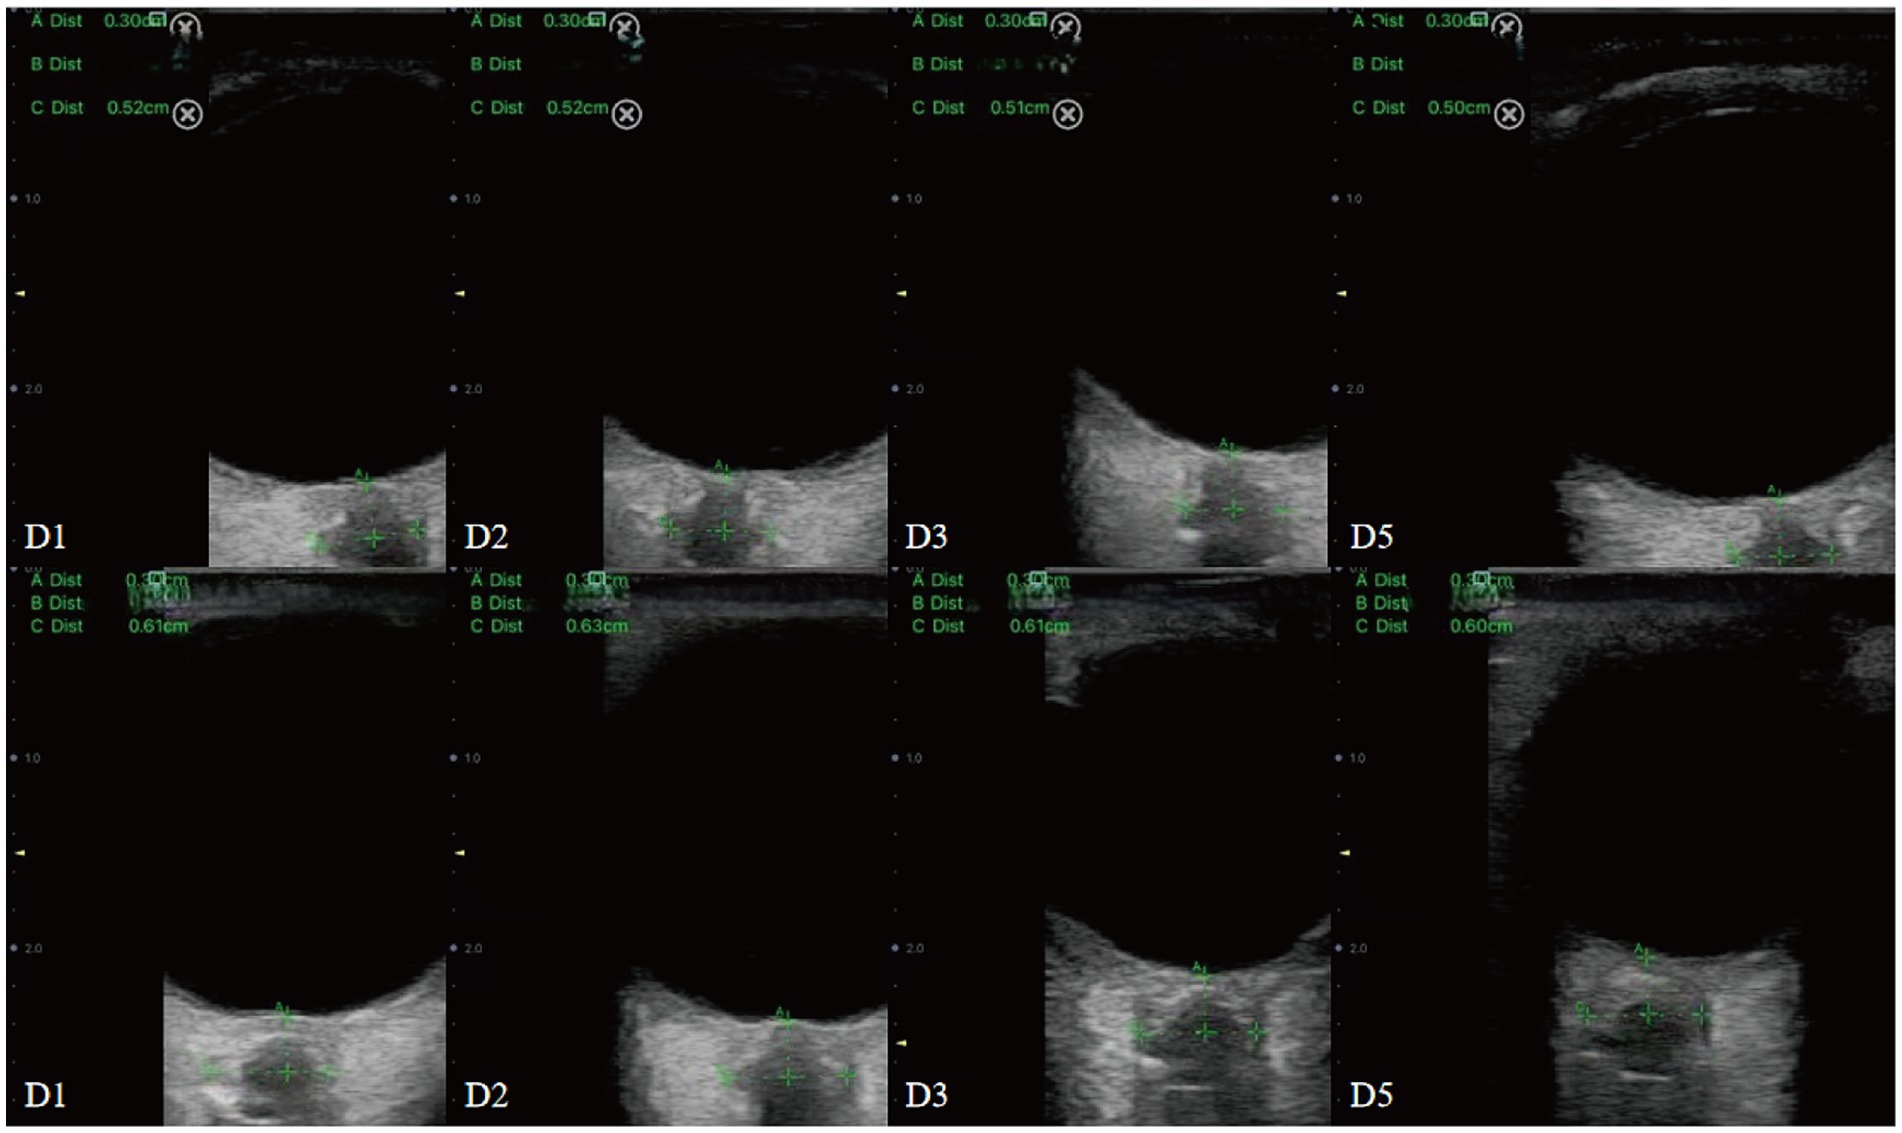

The initial ONSD measurement (D1) was performed at the bedside in the NICU within 48 h after symptom onset. Subsequent measurements were recorded at 24 h (D2), 48 h (D3), and 96 h (D5) after the initial assessment, whenever clinically feasible. All examinations were conducted by an experienced neurophysiologist to minimize inter-observer variability, using a portable ultrasound device (Qiyou, China) equipped with a linear probe, in accordance with previously established ONSD measurement protocols (15). These standardized methods contributed to the development of the latest ONSD Point-of-Care Ultrasonography Quality Criteria Checklist (ONSD POCUS QCC) (16).

During the procedure, patients were positioned supine with their head elevated at 20° to 30°, maintaining a neutral head position and keeping their eyelids naturally closed. A sufficient amount of ultrasound gel was applied to the probe, which was gently placed on the closed upper eyelid. The clearest cross-sectional view of the optic nerve without artifacts was selected for measurement. ONSD was measured 3 mm behind the globe, perpendicular to the optic nerve axis (Figure 1). Three measurements were obtained in both the transverse and sagittal planes for each eye, resulting in six values per eye. The average of these six values for each eye was used for data analysis.

Figure 1. Sonographic measurement of the ONSD 3 mm behind the eyeball. The left ONSD was 0.52 cm in a patient from Group 1, and the right ONSD was 0.57 cm in a patient from Group 2.

In this study, four consecutive ONSD measurements were obtained from 18 patients with extended NICU stays (Table 2) to characterize longitudinal ONSD changes in the affected and unaffected sides during the early treatment phase for LHI patients (Figure 5). Due to the limited number of patients with repeated measurements and challenges in longitudinal data collection, the analysis was confined to graphical observation of ONSD trends. These preliminary findings are intended to provide a foundational reference for the design of future longitudinal studies on ONSD monitoring.

Ultrasound images displaying several measurements labeled A, B, and C, each with specific distances in centimeters. Each panel is identified by labels D1, D2, D3, and D5, arranged in a grid. The panels appear to show different sections and angles, with metrics in green text. The central portion of each ultrasound is focused on a specific area with crosshairs and measurements highlighting points of interest.

Figure 5. Dynamic changes in ONSD among conservatively managed patients with improved (upper panel) and deteriorated (lower panel) outcomes.

Line graphs were used to illustrate ONSD changes in six representative patients (Figure 6). Based on discharge outcomes, patients A, C, D, and E were classified into the improved group, while patients B and F were assigned to the deteriorated group. Initial ONSD values exceeded 5 mm in all patients, indicating the presence of ICH within 48 h of symptom onset. Regardless of the treatment administered, the affected- and unaffected-side ONSD curves showed remarkable overlap across all patients. Notably, ONSD values decreased over time in the improved group but increased in the deteriorated group.